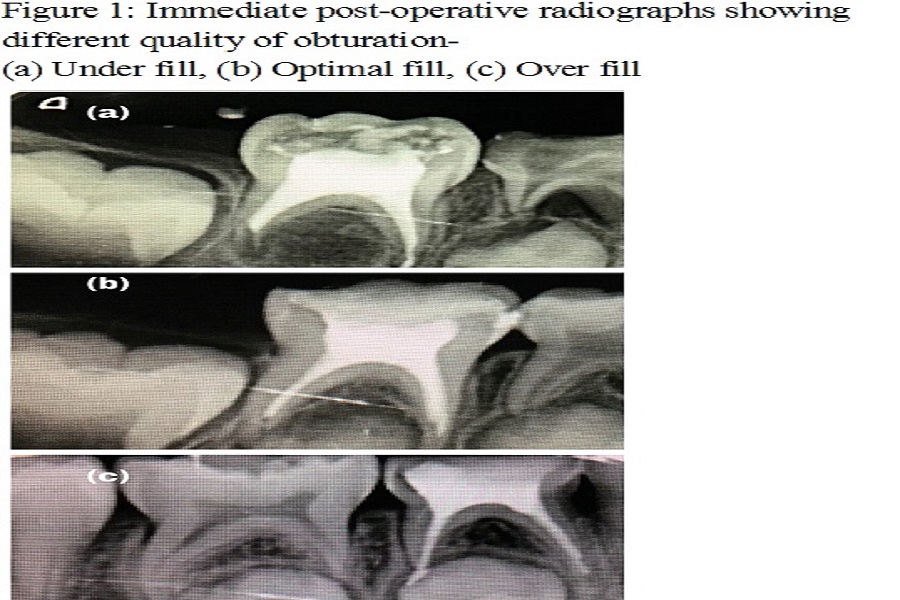

Objective: Pulpectomy is the conservative treatment approach that retains and preserves the primary tooth in the dental arch in its normal function and non-pathologic state until its exfoliation. Over the years, pulpectomy has been performed using various instrumentation techniques. The aim of this study was to compare the quality of root filing and instrumentation time using Kedo-S files, Reciprocating files and K-files in primary teeth. Material And Methods: A randomized clinical trial was performed on 45 primary molars equally distributed for instrumentation with Kedo-S files, reciprocating files and K-Files. Immediate post-operative digital radiographs were taken to evaluate the quality of root filing and root canal instrumentation time was also recorded. Results: Mean instrumentation time with Kedo-S was 75.6 seconds, reciprocating file was 190.6 seconds and K-file was 95.4 seconds. Highest optimal fill was obtained with Kedo-S file group, highest overfill was obtained with Kedo-S group and highest under fill was obtained with reciprocating file group. Conclusion: Kedo-S rotary system provides better quality of root canal filling in minimum instrumentation time.